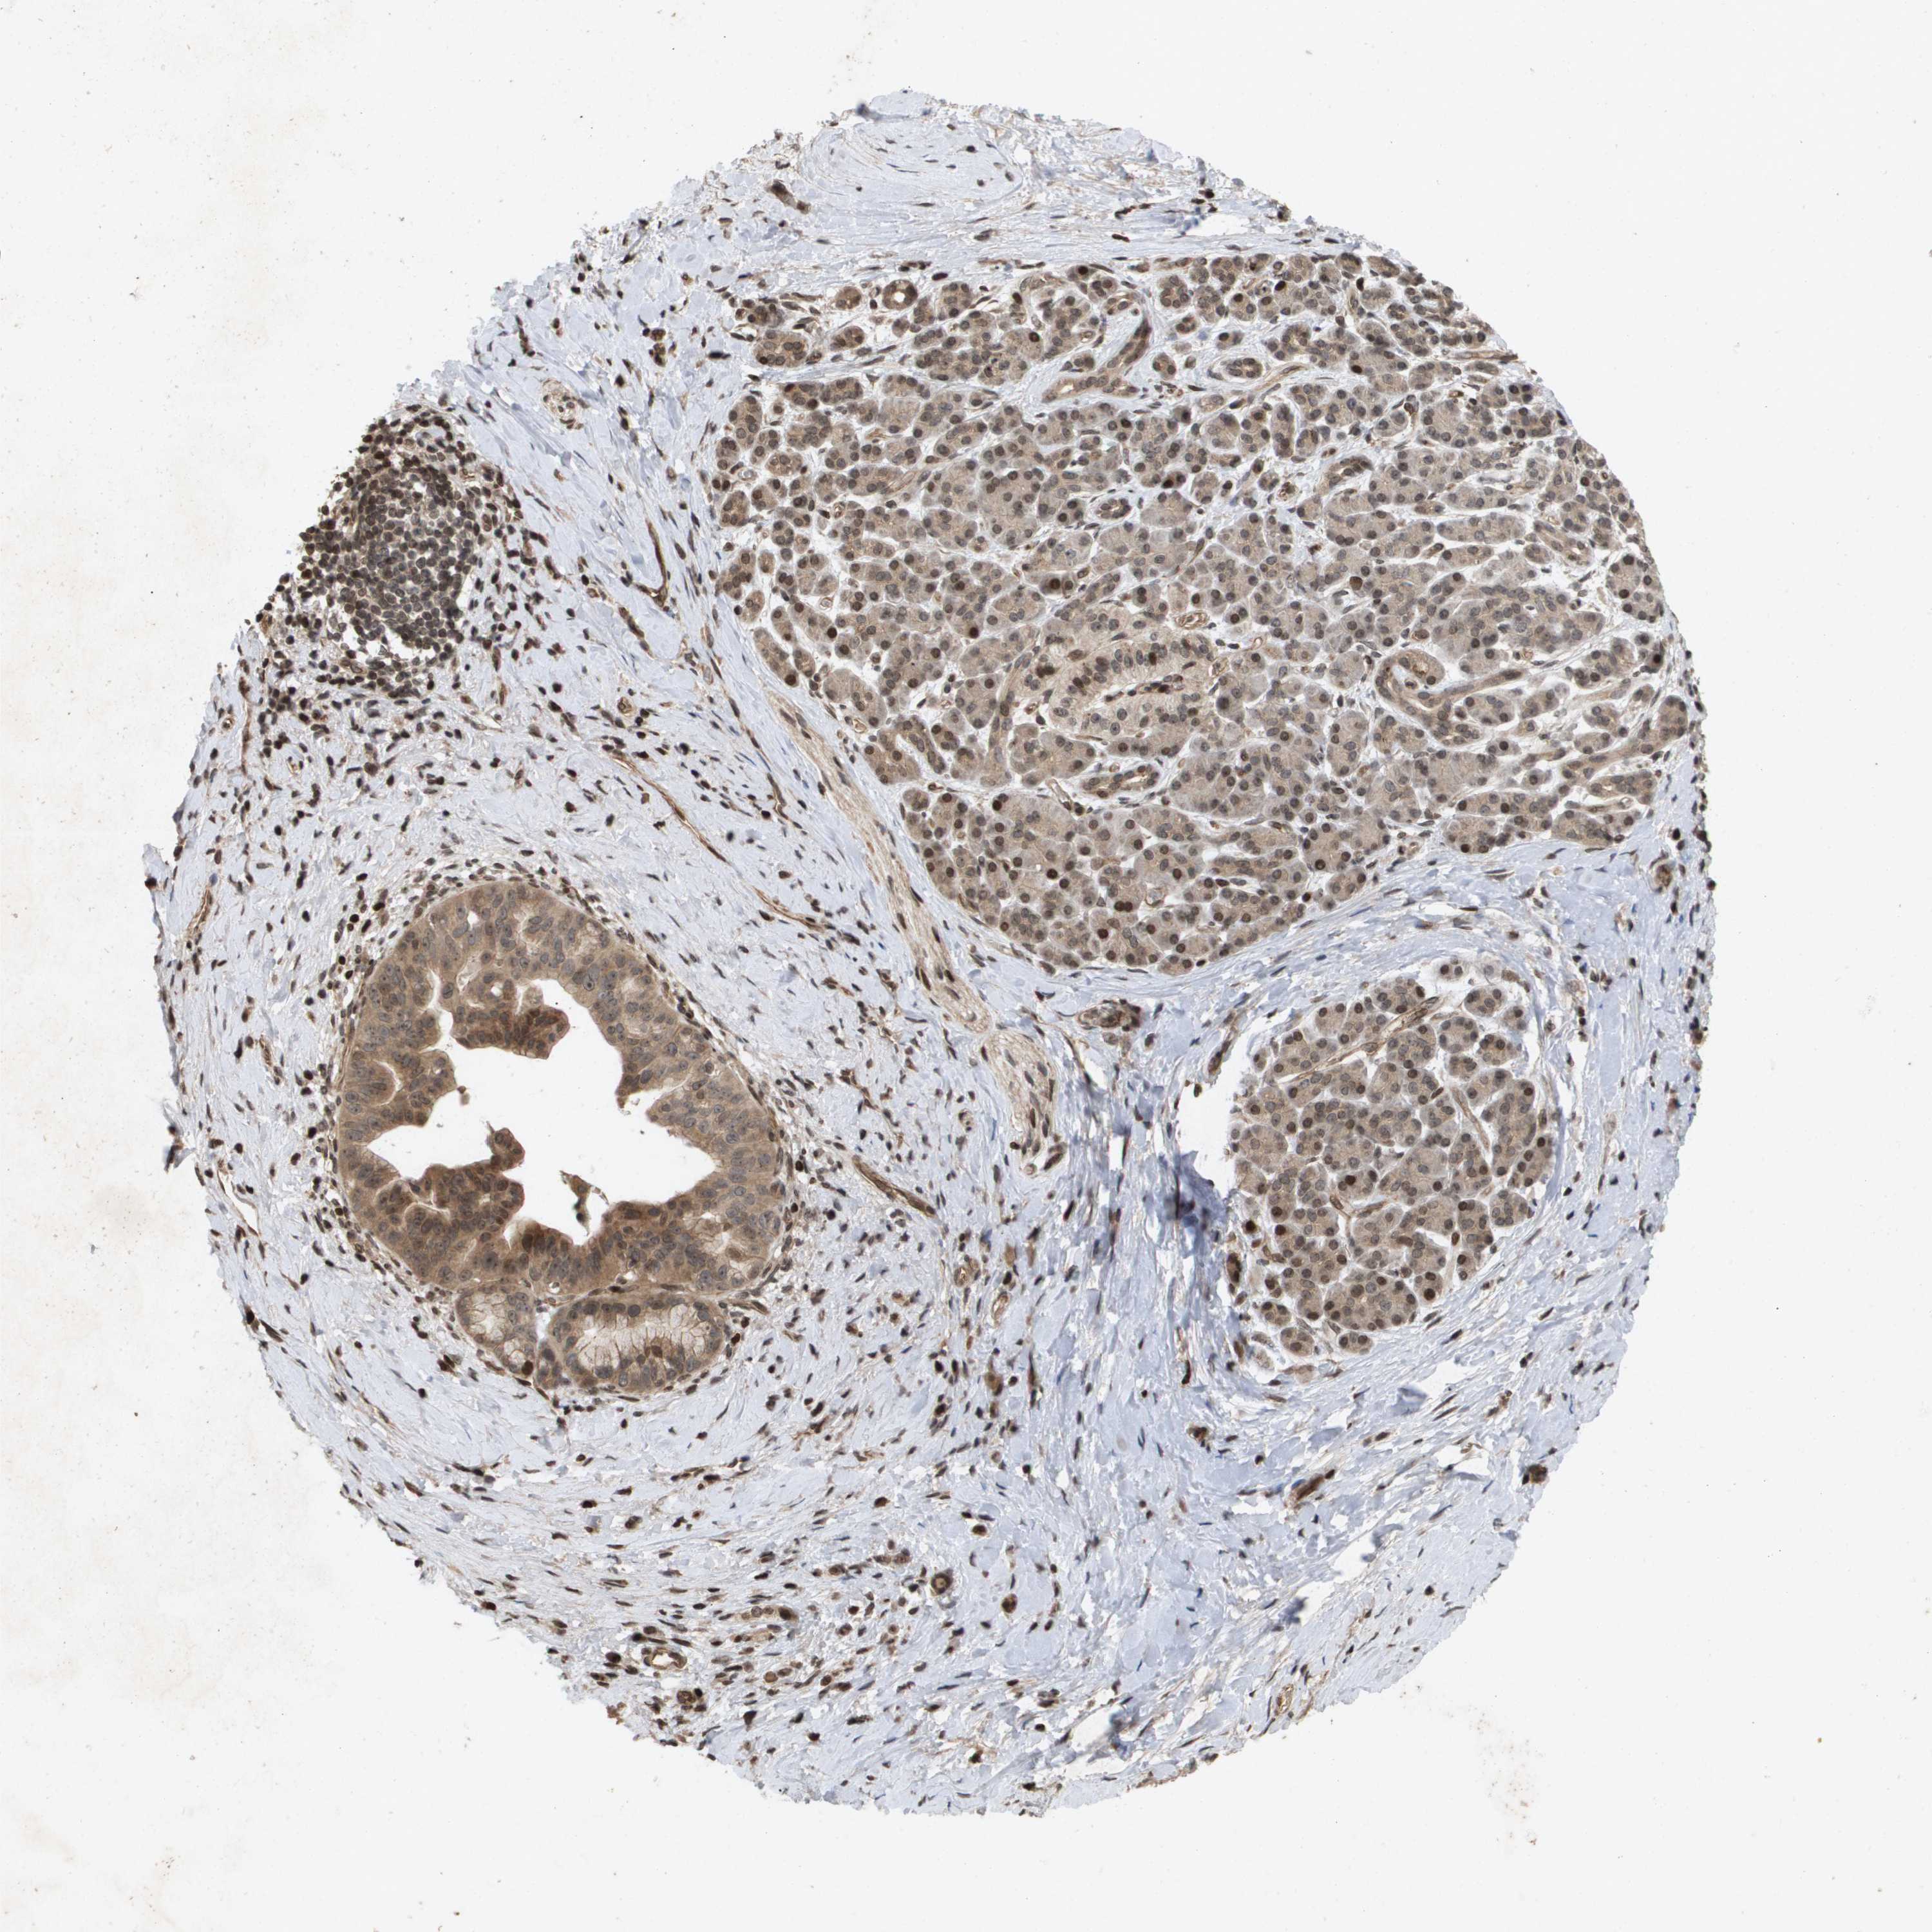

PANCREATIC CANCER - Protein expressioni

A mouse-over function shows sample information and annotation data. Click on an image to view it in a full screen mode. Samples can be filtered based on level of antibody staining by selecting one or several of the following categories: high, medium, low and not detected. The assay and annotation is described here.

Note that samples used for immunohistochemistry by the Human Protein Atlas do not correspond to samples in the TCGA dataset.

Antibody stainingi

Antibody staining in the annotated cell types in the current human tissue is reported as not detected, low, medium, or high, based on conventional immunohistochemistry profiling in selected tissues. This score is based on the combination of the staining intensity and fraction of stained cells.

Each image is clickable and will lead to virtual microscopy that enables deeper exploration of all samples and also displays staining intensity scores, fraction scores and subcellular localization as well as patient and tissue information for each sample.

Antibody HPA028549

Antibody HPA052504

Antibody CAB017452

Staining

High

Medium

Low

Not detected

Intensity

Strong

Moderate

Weak

Negative

Quantity

>75%

75%-25%

<25%

None

Location

Nuclear

Cytoplasmic/membranous

Cytoplasmic/membranous,nuclear

Adenocarcinoma, NOS